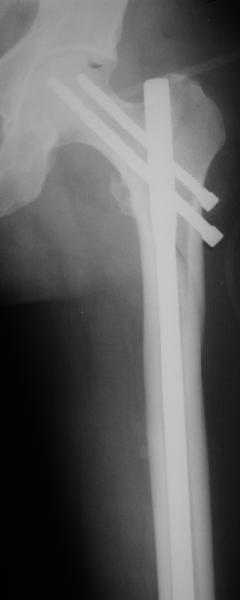

DK> фиксацию провели антеградным штифтом.

Да, сейчас это и у нас самый напрашивающийся выбор. Сделали гвоздем ChM, картинки в приложении.

У молодых реконструкционный гвоздь самое то. При остеопорозе надо что-то помассивнее.

Here are some classification suggestions

(Seinsheimer 5 , AO 31 A2.3 or Russell Taylor 2B - see http://www.hwbf.org/ota/bfc/tonyr2/ft028.html

for your sub-intertrochanteric femur fracture case. Excellent work and technique with the reconstruction nailing.